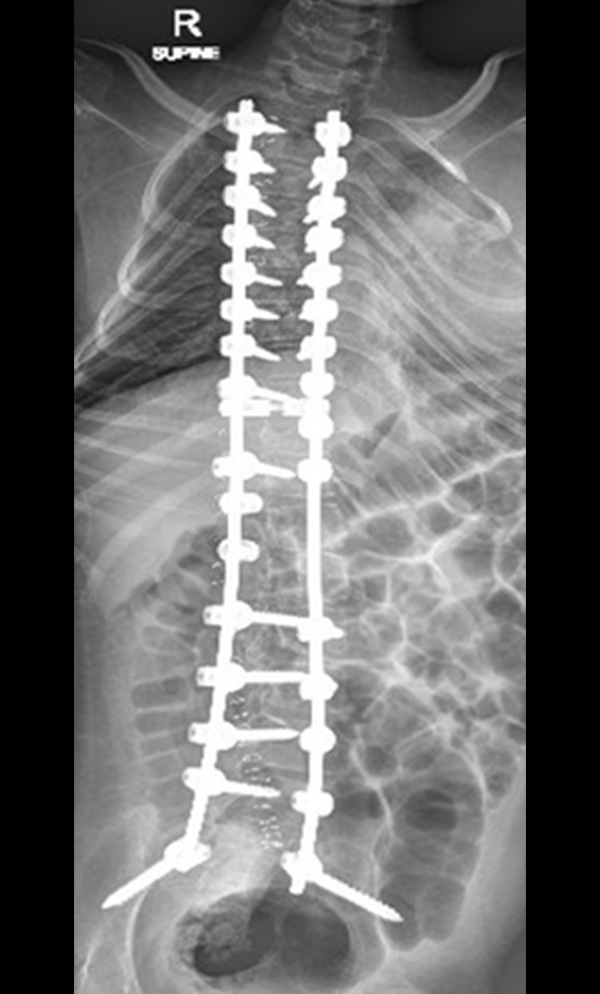

The procedure involves repositioning the spine and securing it with Screws and Rods. Bone graft is then placed so the treated vertebrae gradually heal together into one solid segment. This creates long-term stability, preventing further curve progression and improving overall alignment.

The surgical procedure typically involves Long-Segment Stabilization using Screws and Rods, and may also include Pelvic Fixation. The goal of the surgery is to improve overall alignment, sitting balance, and long-term care needs. Due to the medical complexities of these patients, a Multidisciplinary Approach is essential in planning the surgical intervention.

Gallery : Before - After

After

Before